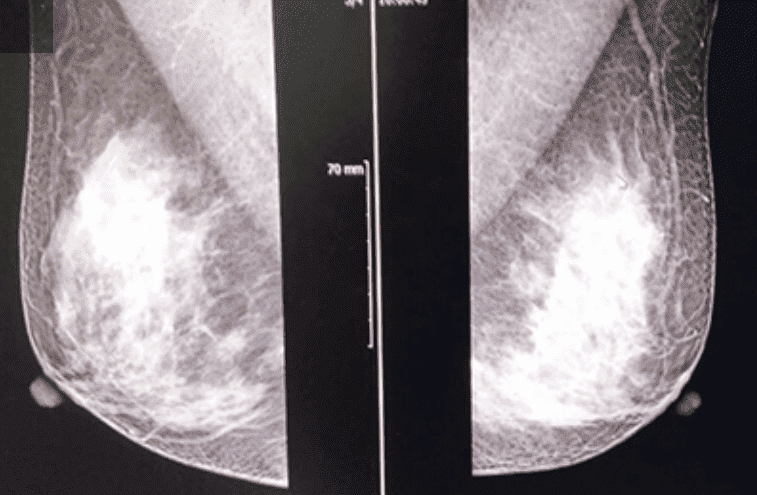

유방암

유방암이란 ?

유방은 여러 종류의 세표들이 모여 있는 장기입니다. 이 세포들 각각에서 암이 발생할 수 있으므로 유방암의 종류도 다른 장기의 암에 비해 많은 편입니다.

하지만 대부분의 유방암은 유관에서 기원하여 이를 관암종이라고 합니다.

유방암 검진

유방암 검진의 목적

조기유방암을 발견하여 조기치료로 생존율을 높이기 위함입니다.

새로운 유방암 검진 방법 (미국 암학회 권고)

기존의 유방암검진을 보완하기 위하여 새로운 권고안이 제시되었습니다.

• 유방촬영 : 매년